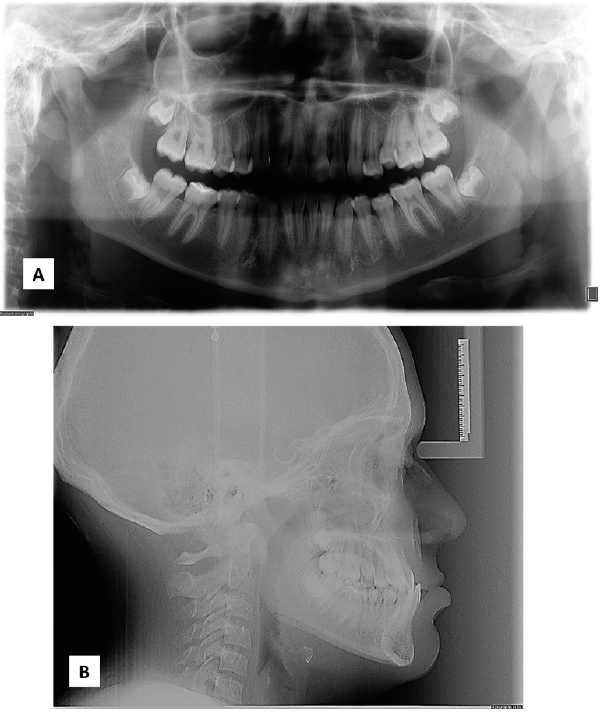

Paciente masculino de 12 años que asistió a la clínica de ortodoncia de la DEPeI de la Facultad de Odontología UNAM, donde tenemos sus registros fotográficos (Figura 1), radiológicos (Figura 2) y digitales (Figura 3). El diagnóstico facial consistió en un perfil cóncavo, proquelia inferior y biotipo euriprosopo. Cefalométricamente el paciente presentó Clase III esquelética combinada por retrusión y prognatismo, con un tipo de crecimiento horizontal (Figura 2.B). Dentalmente, clase III molar y canina bilateral y mordida cruzada anterior.